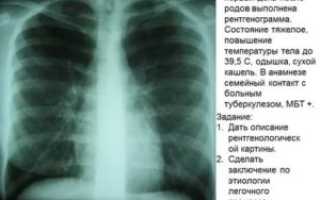

Пневмония, или воспаление лёгких, отчётливо просматривается на рентгене. Правда, на начальной стадии могут возникнуть сложности. Вот что можно увидеть на снимке при воспалительном процессе:

- очаги воспаления в виде затенений различного размера;

- уровень поражения органа;

- воспалённую плевру и бронхиальное дерево;

- расширение корня лёгкого, как реакцию лимфатической системы на заболевание;

- усиление лёгочного рисунка.

Очаги воспаления могут иметь размеры до 1,5 см. Форма инфильтрата может быть любой. Размер поражённой области оценивается на фронтальном и боковом снимках.